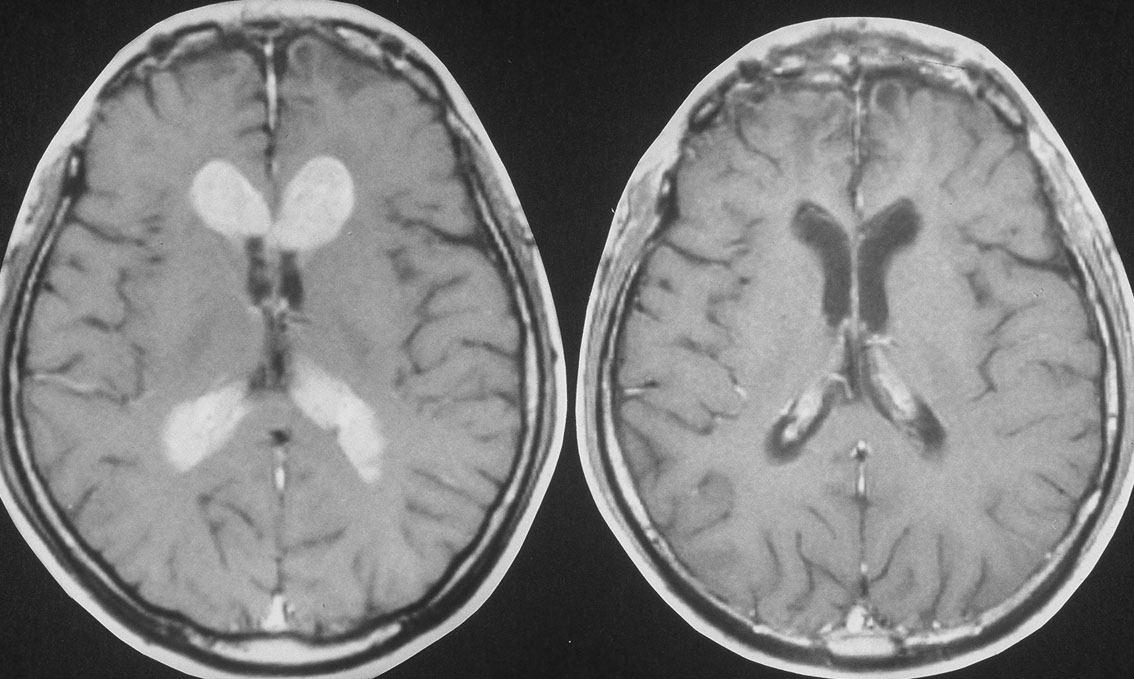

リンパ節胚芽中心 germinal center

左側は腫瘍細胞のみで構成される組織で,右側はリンパ節胚芽中心 germinal centerを形成するように多くのリンパ球が集簇する組織です。腫瘍細胞は未分化で大型,単純にシート状に配列することが多いです。豊富な細胞質にはグリコーゲンが蓄積して明るく見え,中心に大きな核があります。本来は増殖能の高い腫瘍であり,MIB-1染色率は高く分裂像がみられます。

fibrogliosisとリンパ球浸潤が優位で腫瘍細胞が少ない部分もあります。その変化が強い組織をdesmoplastic stromal responseといいます。granulomatous germinomaと呼ばれるものでは著明な肉芽腫様の炎症反応像 granulomatous response をみることもあります。

この所見は,MRIで描出されないような大脳基底核germinomaなどで,germinoma cellsの増殖と退縮が繰り返され,gliofibrosisに置き換わりながら存在して腫瘍としてのmass effectを呈しないという臨床像と一致します。